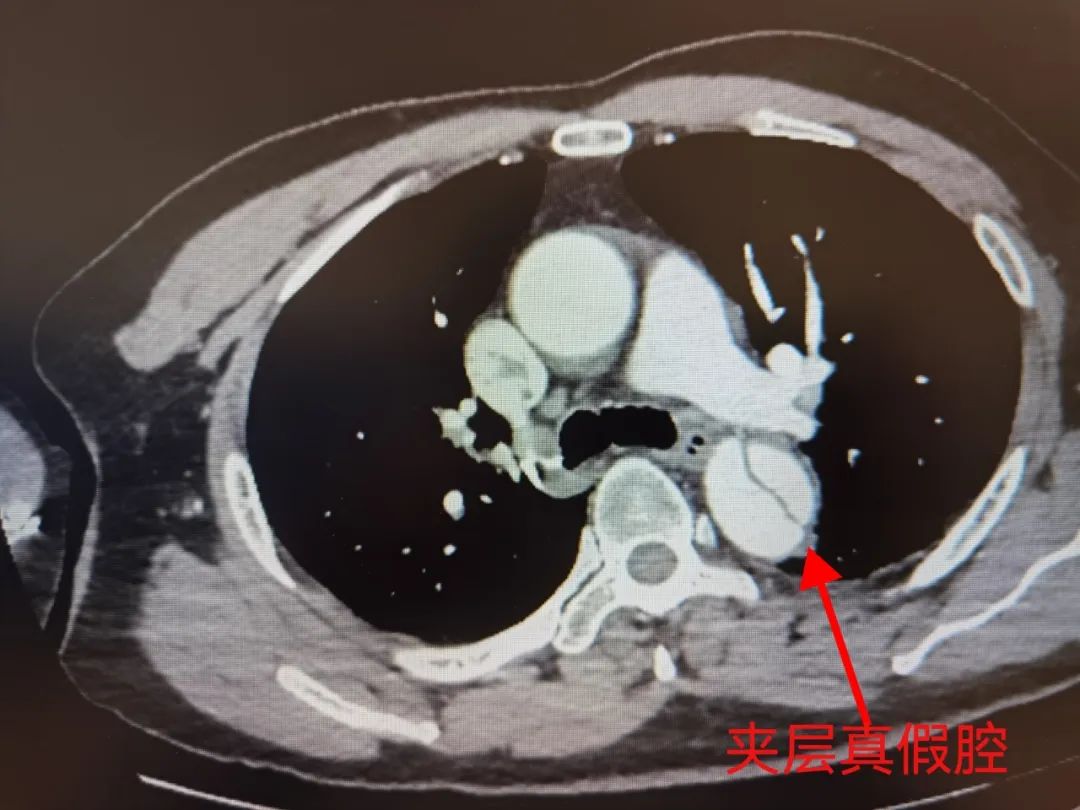

快速完成胸腹主动脉血管造影CTA

证实为胸腹主动脉夹层

双肾动脉夹层

右侧髂总动脉夹层

主动脉夹层是一种紧急的血管疾病,通常发生在主动脉壁的内膜和中膜之间形成的裂缝处。这种裂缝会导致血液穿过夹层,形成一个假性的血管腔,增加了主动脉壁的压力和脆弱性。

主动脉夹层的诊断通常通过临床症状、体格检查和影像学检查来确认。其中,血管CTA扫描是最常用的检查方法,可以直观地显示主动脉夹层的位置和程度。